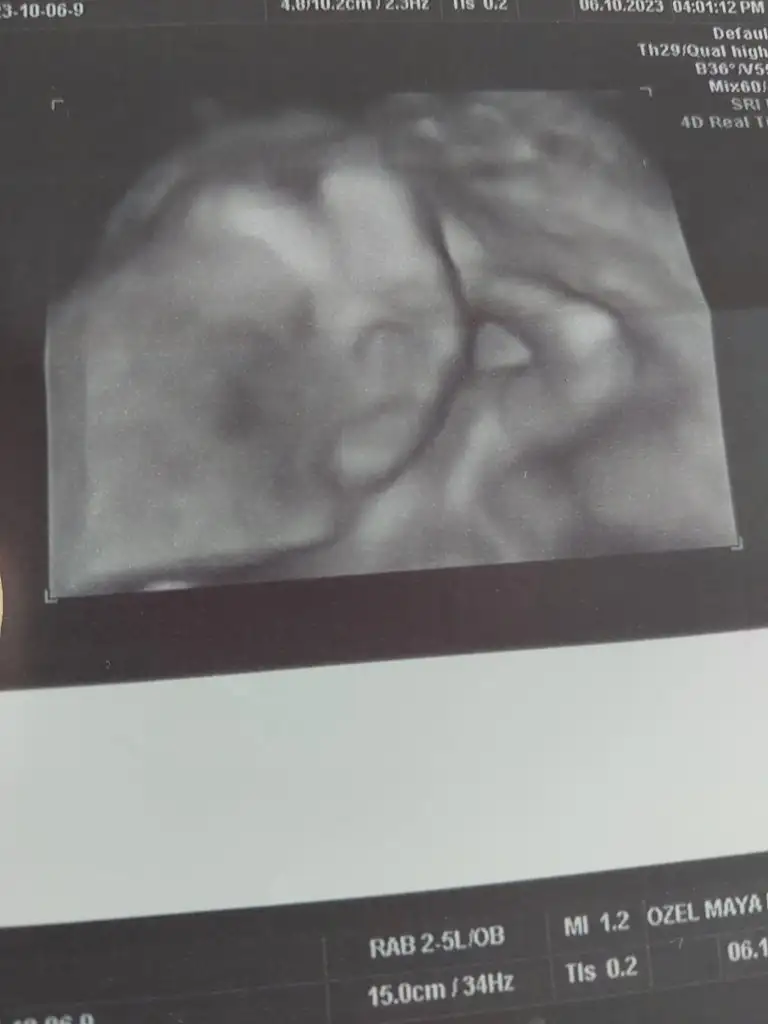

Kiz dedi doktorNeymiş cinsiyeti kuzunun

Sağlıkla gelsinBugün ki ultrason fotoğrafı